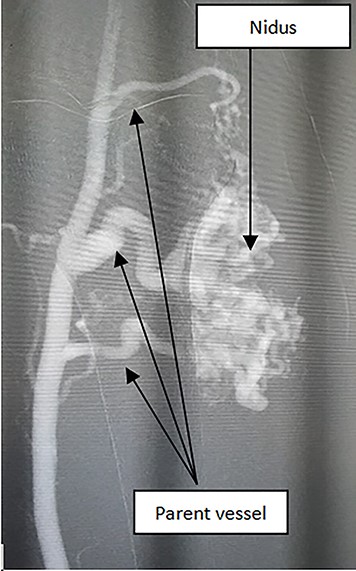

AVM embolization was performed through antegradely femoral approach; white arrows: the existence of feeding arteries need to be occluded; blue arrows: nidus and feeding arteries are being occluded by NBCA/Lipiodol; (asterisk) nidus and feeding arteries were totally occluded.

The patient had undergone an embolization (Fig. 2) and a surgical excision after 4 days (Fig. 3). The mean volume of injected NBCA/Lipiodol 12.5% was 15-20 mL. Clinical symptoms were medium pain and swelling. These symptoms decrease gradually and disappear within 4 days. No long-term peripheral circulation or pulmonary deficit was noted during the period of follow-up.